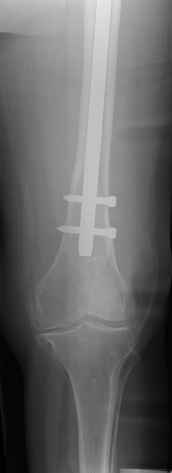

3. Retrograde nail (small diameter in large bone) does not allow for good, stable fixation (often malalignment) and early weight bearing (I have seen the locking screws and nail cutting through the distal femur into the knee joint - in osteoporotic bone, heavy persons)

4. We could treat this fracture like there is no a nail - new locking plates allow for secure fixation.... two similar cases are attached...

Gamma nail exchange may probably fit the criteria of optimal and minimal invasivness, indeed. Removal could be relatively fast due to large intramedullary diameter seen on X-ray.

I do agree that distal locking of the nail in distal femur remains critical.